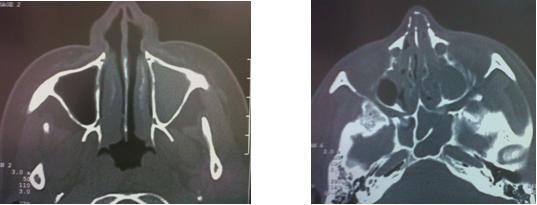

Si se diagnostica una sinusitis crónica, (generalmente apoyado es estudios de gabinete como la tomografía de senos paranasales) el tratamiento debe ser intensivo con antibióticos y demás medidas como los lavados nasales. Si el problema es persiste, puede ser necesaria una cirugía para limpiar y drenar los senos paranasales afectados.

(foto de tc spn y de qx nasal)